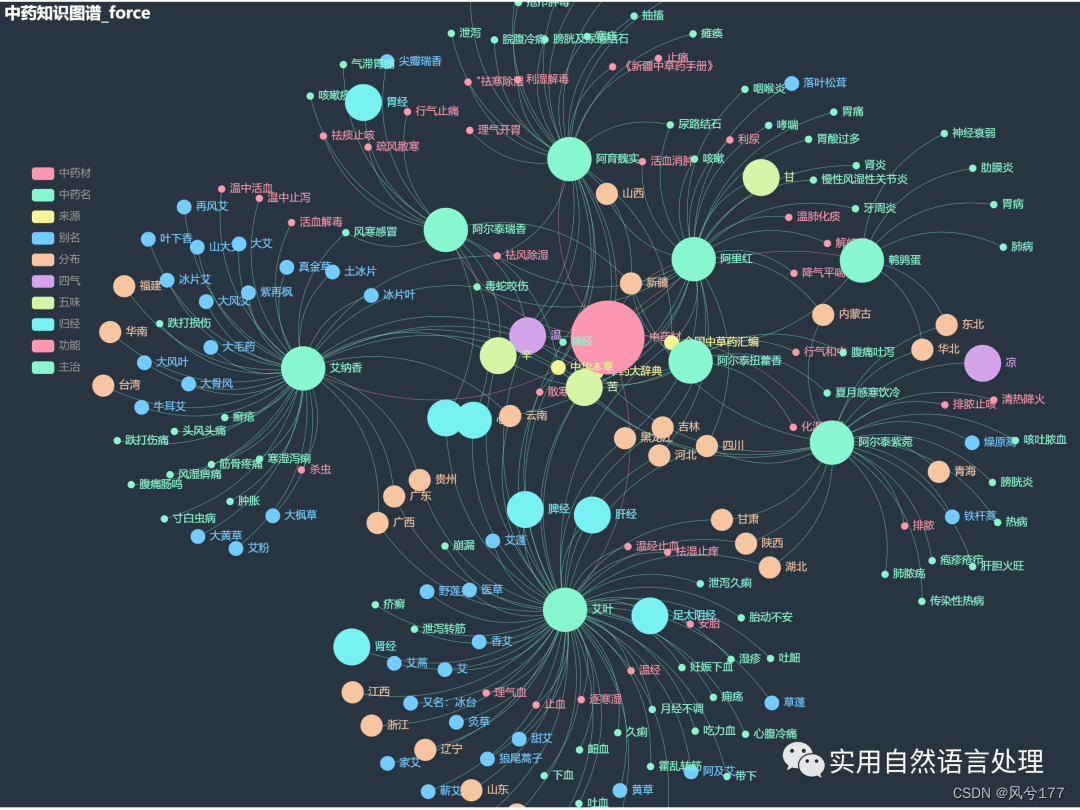

少量数据的中药知识图谱-力导图

较多数据的知识图谱可视化效果

本文将基于pyecharts框架,对中药材知识图谱进行“力导图”和“环形分布”可视化,同时,对中药材地理分布、来源和别名关系进行分析与可视化。

2.2 中药材知识图谱可视化

前文自顶向下构建中药知识图谱初探已经介绍了中药材知识图谱的构建和neo4j可视化过程,接下来将对该图谱数据利用pyecharts进行可视化。